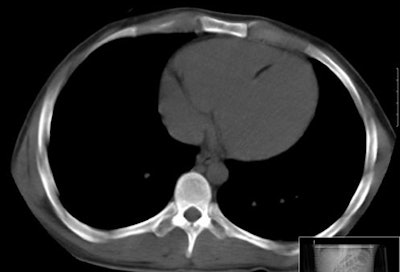

The study revealed foci of fat attenuation within the myocardium in 35 (64%) of 55 patients with TSC. Ranging in size from 3 x 1 mm to 62 x 31 mm, the fat was well circumscribed and focal. The majority of foci were found in the interventricular septum and left ventricle wall, with a few others in the right ventricle wall and papillary muscles.

"This location differs from intramyocardial fat in the right ventricle that has been described in healthy patients and in patients with arrhythmogenic right ventricular dysplasia (ARVD)," they wrote.

In addition, ARVD patients show a more diffuse fat infiltration as opposed to the focal mainly ovoid fatty foci seen in TSC patients in the study, they noted. No enhancing regions were seen in the fatty foci in TSC patients, in contrast to foci seen in patients with primary cardiac hemangioma.

| Myocardial fat in patient with tuberous sclerosis complex at CT. Image courtesy of Dr. Miraude Adriaensen. |

"Despite incomplete depiction of the heart with CT, the majority of patients with TSC demonstrated well-circumscribed foci of fat attenuation in the myocardium that were not present in age- and sex-matched control subjects," Adriaensen and colleagues wrote. "This suggests that such fatty foci may be another characteristic of TSC."